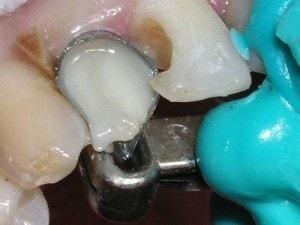

Greater Curve standard in place

Matrix trimmed labially. Contact openings made. Wood wedges are lightly placed to secure the matrix only. The wood wedges are not used to force the teeth apart. Wedging in the traditional sense is not necessary, since the contacts will be a direct build against the adjacent teeth. In lieu of using a retainer Triad Gel holds the matrix in the proper position.

first increment of flowable

Matrix held against the mesial of #6 while the first increment of flowable was placed. This procedure locks the matrix against the mesial of #6.